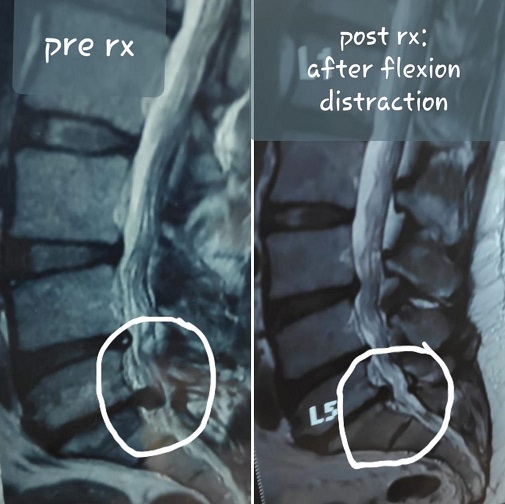

Flexion Distraction

3: Flexion Distraction